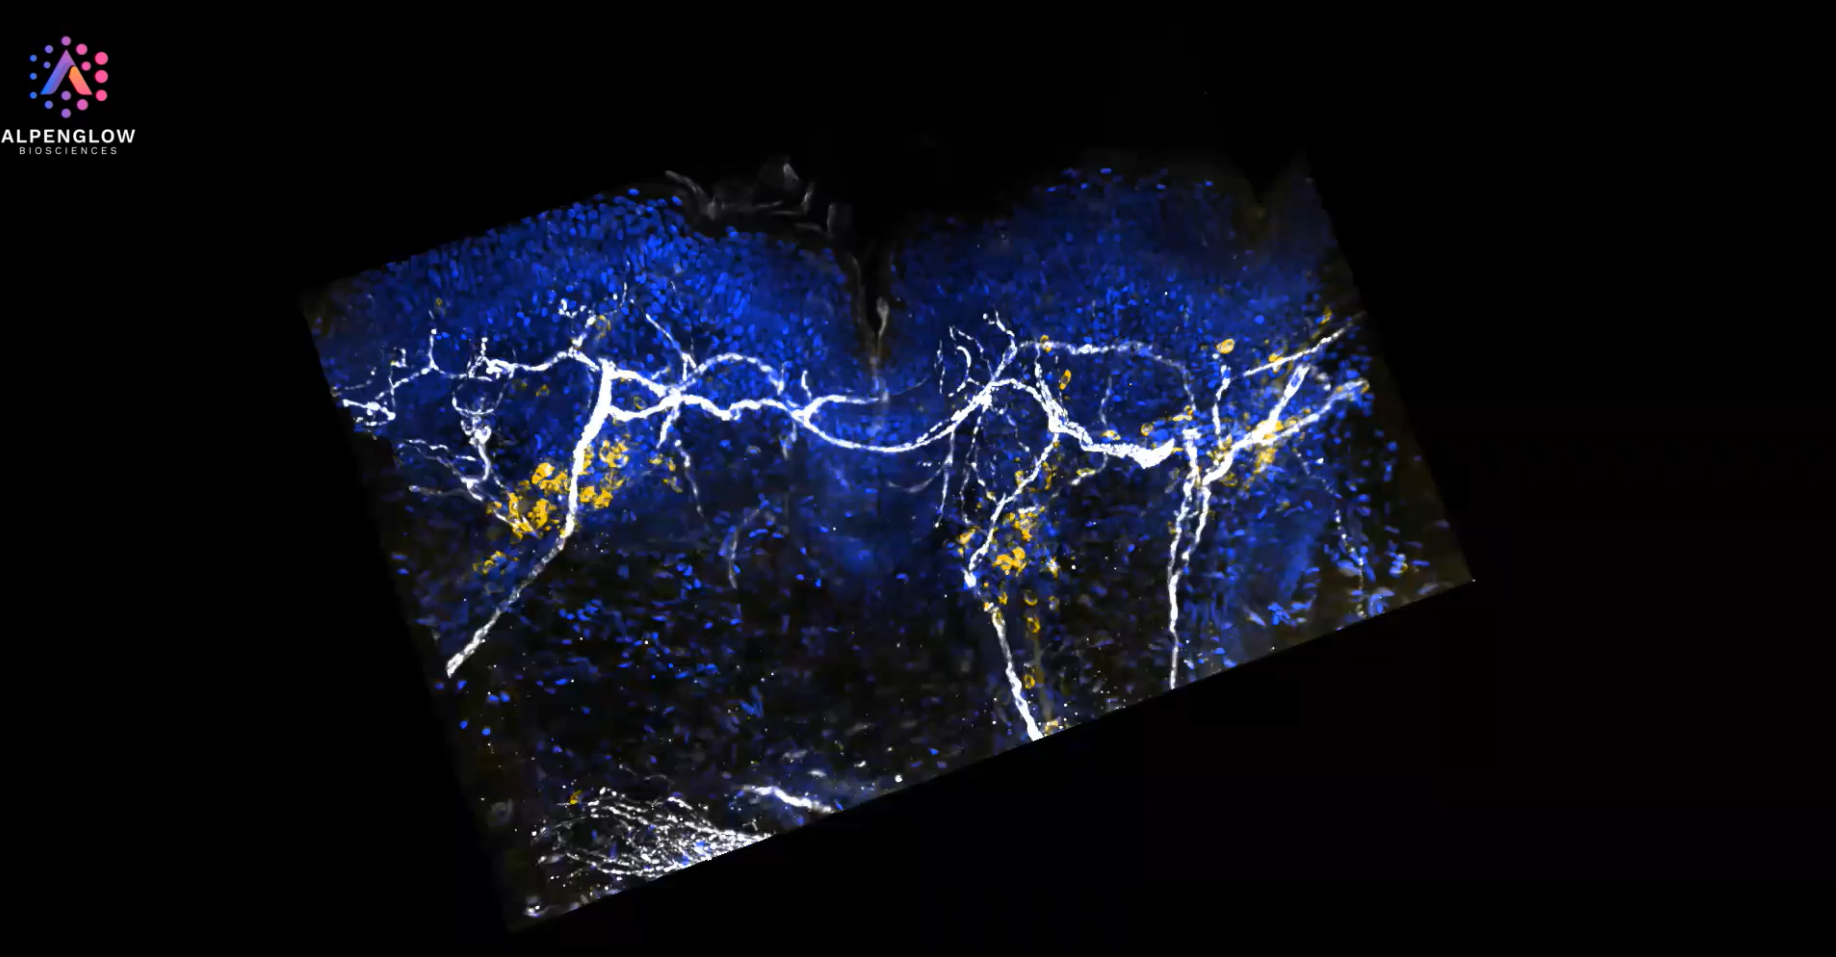

Lymphocytes Cluster Near Nerves in Atopic Dermatitis

Delve into the intricate details of a lesional atopic dermatitis sample captured with cutting-edge 40X high-resolution 3D imaging. The sample is vividly stained with TO-PRO-3 blue for nuclei, PGP 9.5 white for nerves, and CD45 yellow for lymphocytes. Marvel at the precise preservation of epidermal and dermal structures and the clear visualization of immune-cell clusters in close proximity to specific nerve fibers.